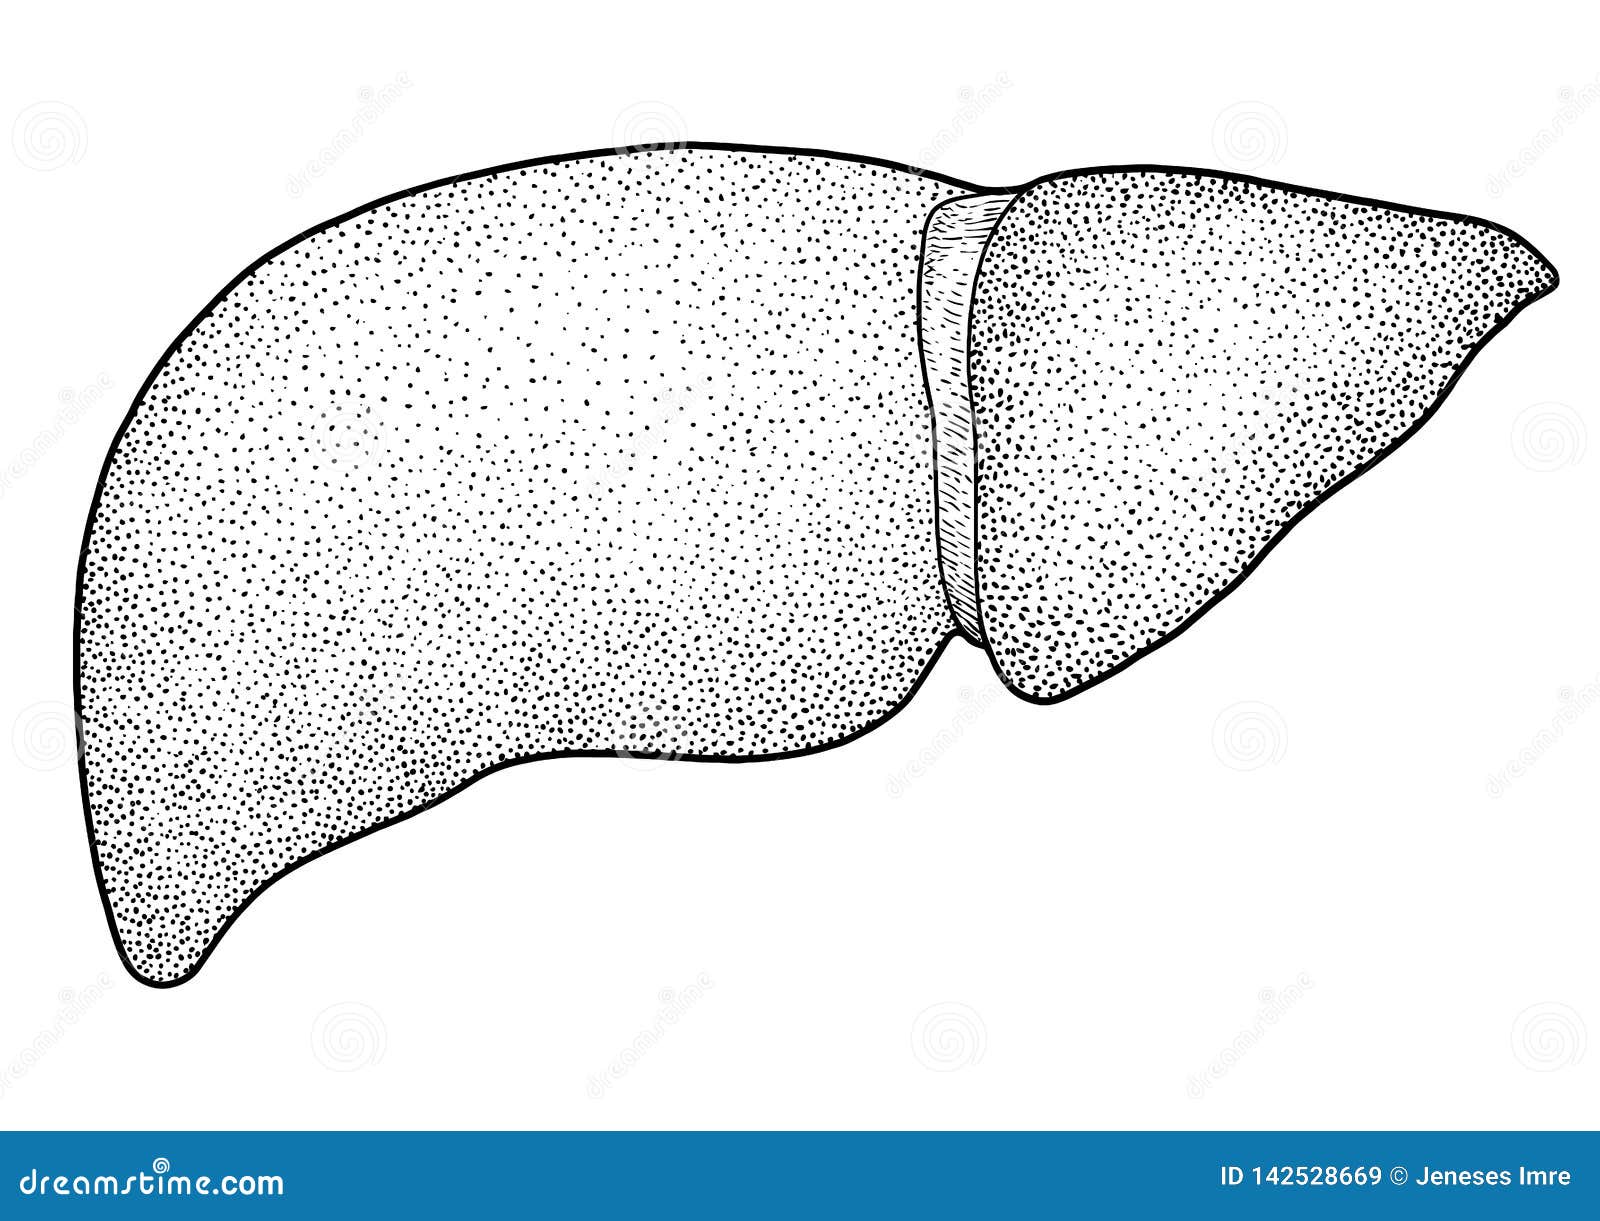

Печень, один из самых крупных и важных органов человеческого тела, выполняет множество жизненно необходимых функций, включая фильтрацию токсинов и производство жизненно важных белков. В данной статье мы рассмотрим, как наглядные изображения печени могут помочь лучше понять её структуру, функции и возможные заболевания. Использование рисунков и диаграмм делает сложные биологические процессы более доступными для понимания, особенно важно это для студентов, врачей и пациентов, стремящихся глубже изучить этот ключевой орган.

Печень рисунок